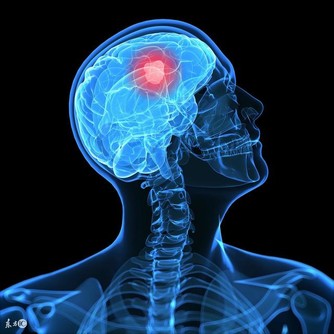

情緒暴躁導致乳腺疾病的發生;乳房的內測與腎經有關,乳頭及乳暈與胃經和肝經有關,乳房外側與肝經、膽經、心包經有關。這幾條經絡任何一條出現阻塞都有可能引髮乳房疼痛,如果這種淤堵不能疏通開來,甚至逐年增加,就有可能發生危及生命的乳腺癌,所以及時疏通與乳房想通的經絡是預防和治療乳腺疾病的關鍵,而各條經絡的氣血充足,則是乳房保養的根本。